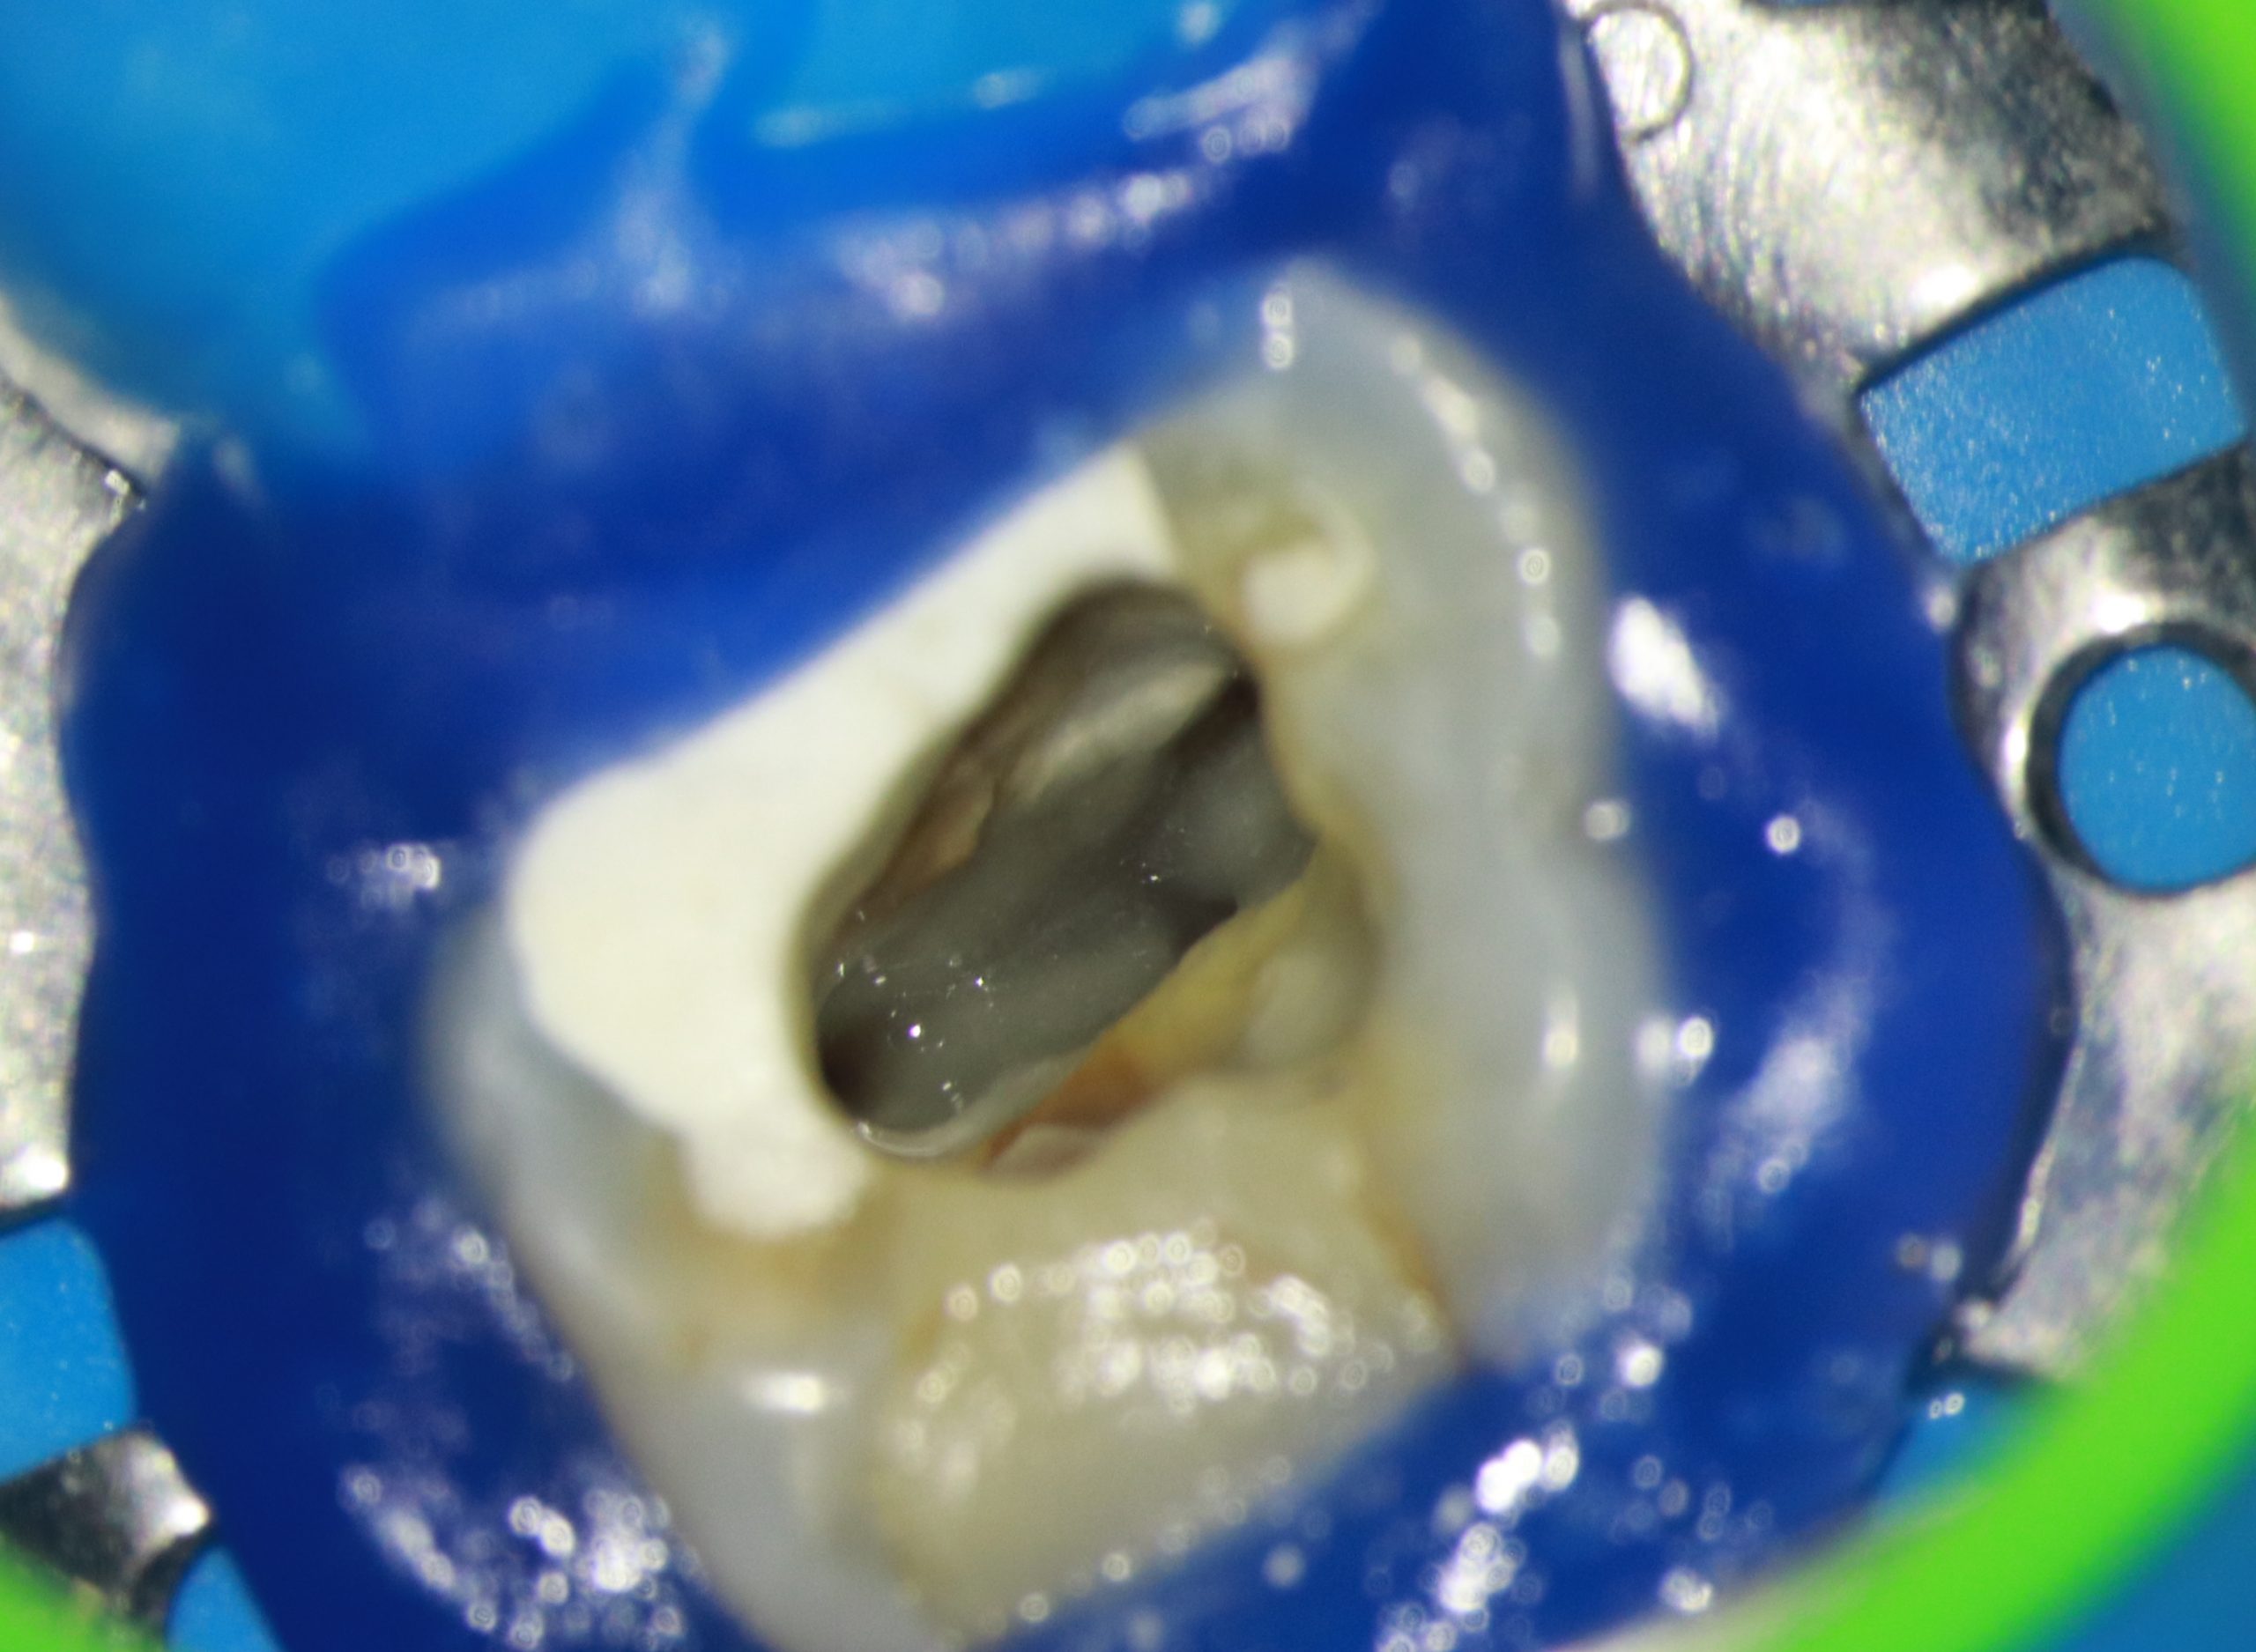

- Depois de anestesia e isolamento absoluto, realizamos o acesso endodôntico com uma broca de alta rotação 1014 de haste longa, utilizada em contra ângulo elétrico. O acesso aos canais foi complementado com inserto ultrassônico esférico com a finalidade de desgastar pouca estrutura dental para localizar os canais.

- Logo, o sistema escolhido para a instrumentação dos canais vestibulares foi o TruNatomy, por causa de sua atresia e curvatura. Para a instrumentação inicial foi usada a lima de pré-alargamento TruNatomy Orifice Modifier e após isso, uso de limas C pilot 8, 10 e 15.

- Após a odontometria eletrônica, utilizou-se a lima TruNatomy para Glidepath.

- Então, para a modelagem nos canais vestibulares, utilizou-se as limas 20.04 e 26/04 (Figura 4).

Figura 2 Figura 3 Figura 4 Figura 5 Figura 6 Figura 7